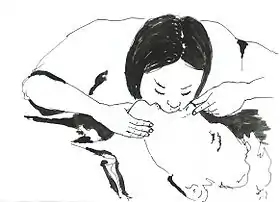

CPR being performed on a medical-training mannequin | |

Cardiopulmonary resuscitation (CPR) is an emergency procedure consisting of chest compressions often combined with artificial ventilation, or mouth to mouth in an effort to manually preserve intact brain function until further measures are taken to restore spontaneous blood circulation and breathing in a person who is in cardiac arrest. It is recommended for those who are unresponsive with no breathing or abnormal breathing, for example, agonal respirations.[1]

In the CPR, the chest compressions push on the lower half of the bone that is in the middle of the chest (the sternum), and the rescue breaths are made pinching the victim's nose and blowing air mouth-to-mouth. If the victim is a baby, the rescuer would compress the chest with only 2 fingers, and would make the ventilations using the own's mouth to cover the baby's mouth and nose at the same time. It is recommended for all victims of any age a general compression-to-ventilation ratio of 30:2 (a continual cycle of 30 rhythmic chest compressions series before each 2 rescue breaths series).[22]: 8

In all the victims, the compression speed is of at least 100 compressions per minute.[22]: 8 Recommended compression depth in adults and children is of 5 cm (2 inches), and in infants it is 4 cm (1.6 inches).[22]: 8 In adults, rescuers should use two hands for the chest compressions (one on the top of the other), while in children one hand can be enough, and with babies the rescuer must use only two fingers.[24]